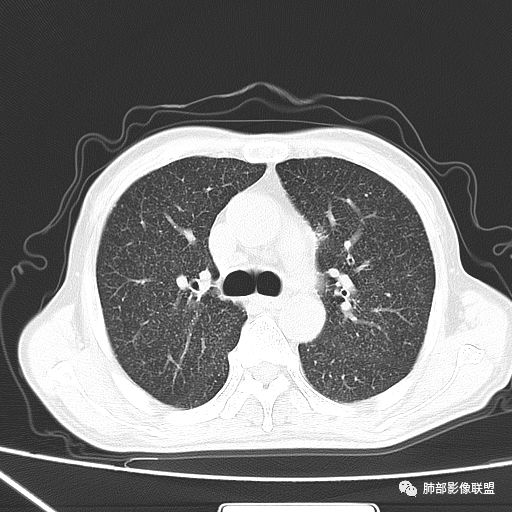

2019年9月12日CT(外院片,手机拍摄)

2019-10-20复查CT如下:

两肺弥漫性粟粒样结节伴左上肺小结节,呈三均匀分布,有结核的临床表现,支持血性播散性肺结核。

大小、分布均匀,边缘清楚

细小结节,弥漫,撒米粒样——血道来源

部分可见分支状

边缘稍平直

毛刺细弱

还是支持结核

血道来源的病灶,均匀、细微,而且部分有分支状,都符合粟粒型肺结核

急性血行播散型肺结核  两肺广泛分布粟粒大小的结节状密度增高影,具有大小均匀、分布均匀、密度均匀的典型“三均匀”特征,注意急性血播病灶非常小,一般粟粒影直径1~2mm。

病灶密集者出现肺外围血管影不清或减少。

发热初期肺部可缺乏典型影像学改变,1到2周后出现的广泛粟粒结节对诊断具有高度提示作用!